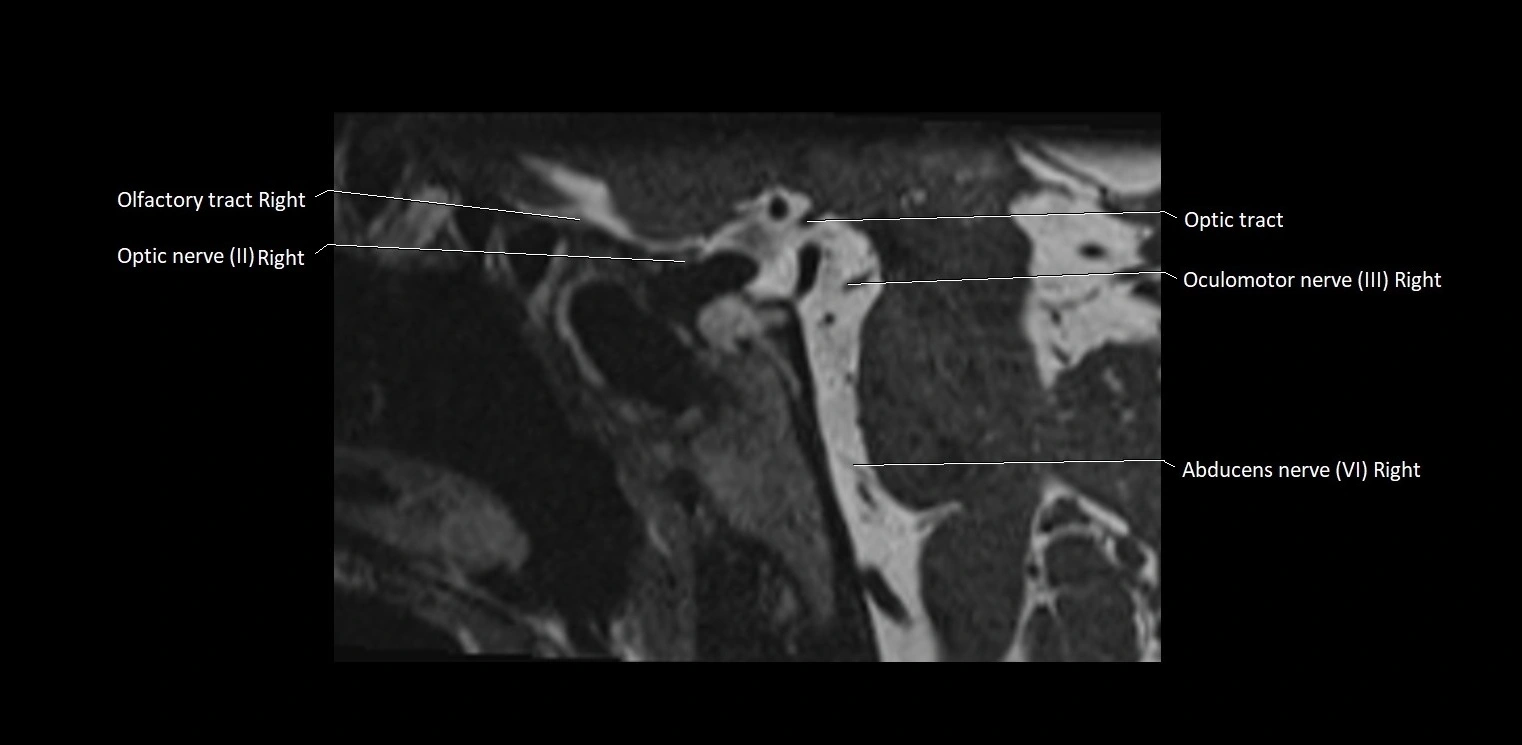

MRI Appearance

• The abducens nerve is a small, thin, linear structure

• Best visualized on high-resolution T2-weighted 3D MRI sequences (e.g., FIESTA or CISS)

• Seen as a hypointense (dark) line running from the brainstem at the pontomedullary junction, traversing the prepontine cistern, and entering Dorello’s canal under the petrosphenoidal ligament, then into the cavernous sinus, and finally the orbit

• May be challenging to visualize in standard MRI due to its small size

• Pathology may be inferred by absence, displacement, or enhancement of the nerve

MRI images

image